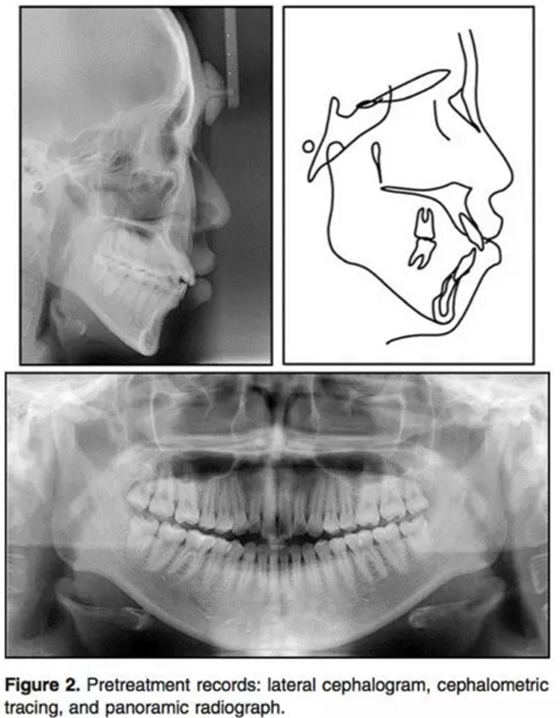

輔助檢查:側(cè)位片:骨性II類(ANB3.5°);下頜后縮(N per to Pog,-4.5°);高角(PFH/AFH, 59.5%; MP-FH, 32.7°)。上頜切牙輕微前突,下頜切牙突度正常(U1 to FH, 120.7°;IMPA, 90.0°)。上頜前后牙都垂直向發(fā)育過(guò)度(U1-PP, 36.9 mm; U6-PP, 27.9mm) 。上前牙在休息位時(shí)暴露量相對(duì)過(guò)量(U1 to stomion, 4.8 mm) 。咬合平面角正常(OP to FH, 12.8°)。此外,下頜垂直向高度也長(zhǎng)于正常值 (L1 to mandibular plane, 47.7 mm; L6 to mandibular plane, 37.0 mm;Table 1) 。